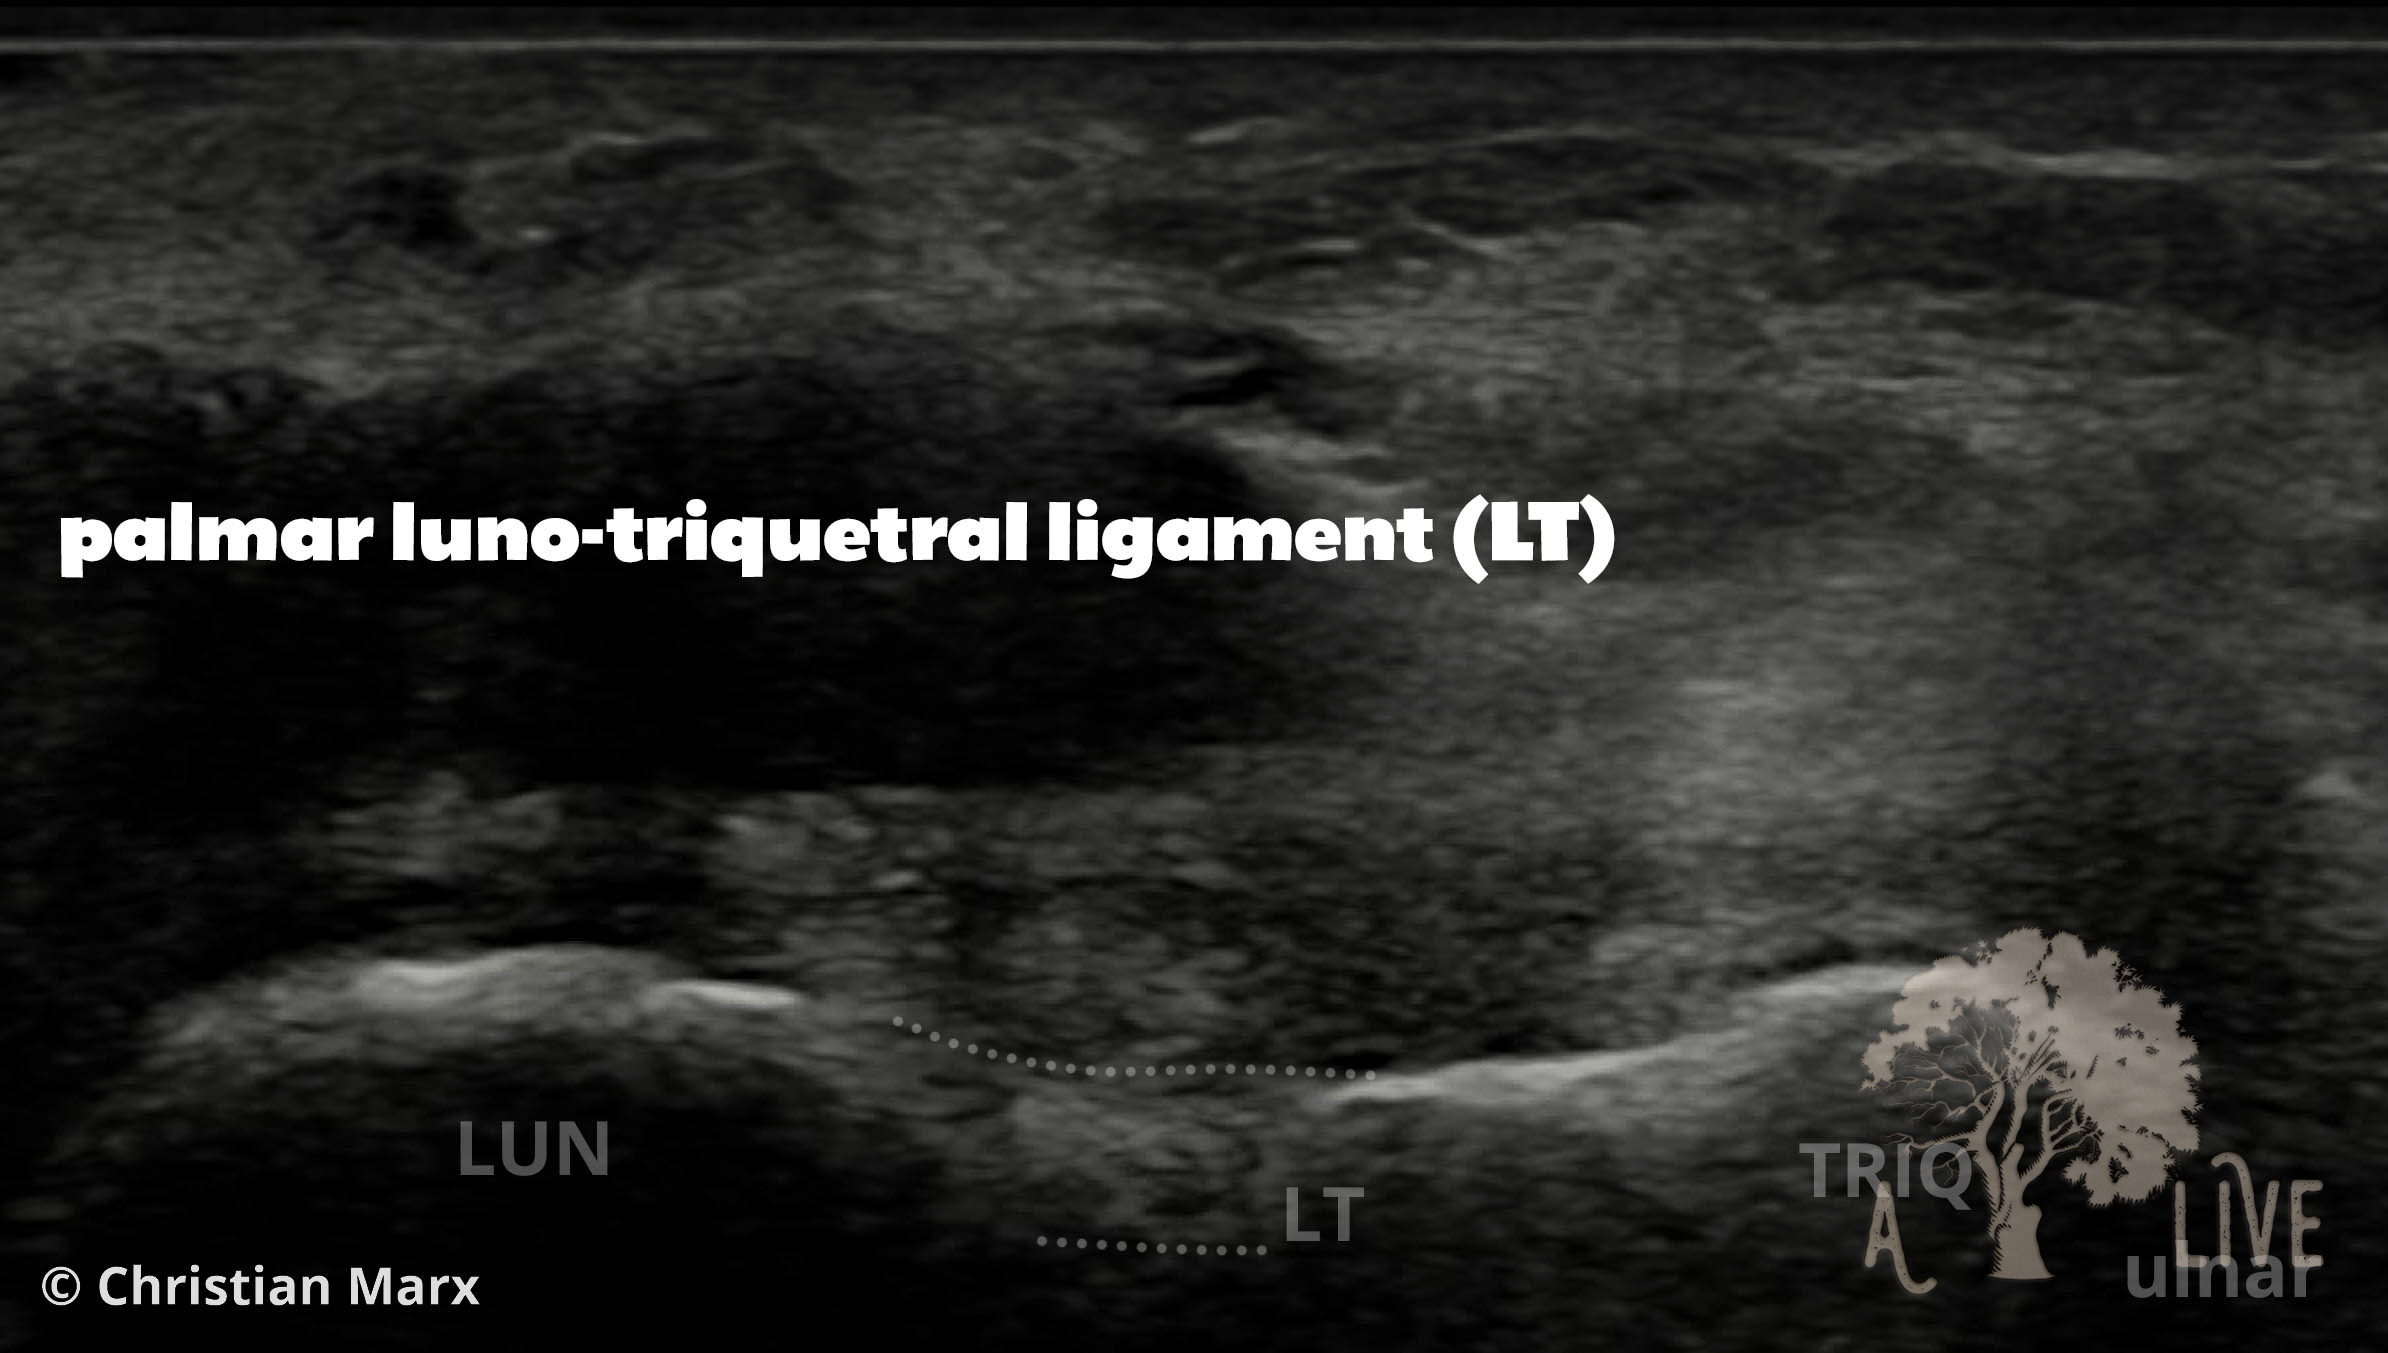

carpal ligaments